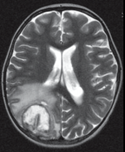

иммунодефицитами. Заболевание приобретает септическую форму. Очень часто вторичные

гнойные очаги возникают в головном мозге. Чаще всего это единичные или множественные

абсцессы мозга различной локализации (Рис.13). Реже отмечают гнойный менингит,

Рисунок13.

Абсцессы головного мозга при нокардиозе.